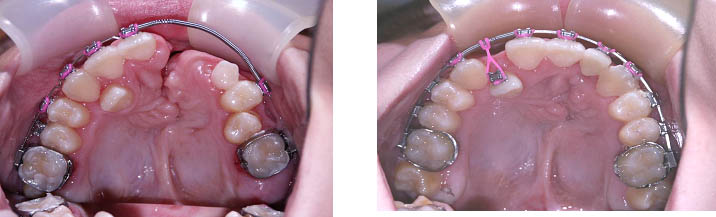

Khám tư vấn điều trị Nha khoa, Chỉnh Hình Răng Mặt